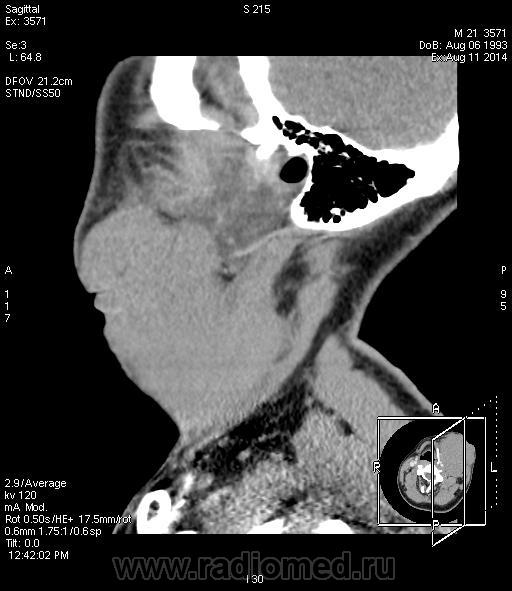

Наблюдение Tatarin

Пролимфоцитарная лимфосаркома высокой степени злокачественноститипа Беркитта.

Еще одна печальная история. "Ужас" нашего городка. (как в передаче Городок) Парень 21 г. Со слов матери в мае '14 года на шее слева образовалась небольшая "шишечка", в поликлинике посмотрели и отправили к хирургу в стационар. С 15.05 по 27.05 находился в  отделении гнойной хирургии с Ds: Острый гнойный шейный лимфаденит слева. В общем хирурги решили удалить лимфоузел, удалили да не весь, гистологи написали что не могут оценить структуру. Удалили да удалили, ах да еще физио назначили, магнитные поля для улучшения микроциркуляции, все дела, только как сказала мать пациента "шишечка" стала "расти как на дрожжах". В итоге пациента выписывают, со словами "мы ничего не можем сделать", сказав матери " мы лечили гнойный лимфаденит, но это не он." crying Оторвать бы им руки... Обратились к знакомому онкологу, взяли биопсию.

Вот такая стремительная динамика...15.05 "шишечка", а дальше-больше, особенно после "лечения" и физиотерапии.

КТ 11.06.14

КТ  11.08.14 (через 2 месяца) после двух курсов ПХТ, перед третьим...растет...